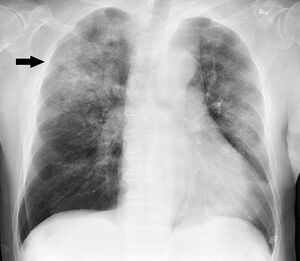

قد يصيب المرض الغازي الناجم عن المستدميات النزلية 6 العديد من الأعضاء. وأشيع أنماط المرض الغازي هو التهاب السحايا والتهاب لسان المزمار وذات الرئة والتهاب المفاصل والتهاب النسيج الخلوي.

• ذات الرئة: قد تكون بؤرية خفيفة أو تتطور إلى تقيح الجنب الشديد.